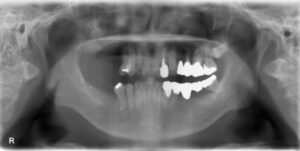

上下顎臼歯5本欠損症例

BEFORE AFTER 55歳男性/上3本・下2本欠損/インプラント埋込手術 【治療内容】 右側上下奥歯のお痛みを主訴…